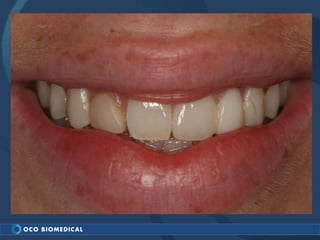

A 3.0mm dental implant was placed to replace congenitally missing maxillary lateral incisors. Dr. Tim Kosinski used a 1.8mm pilot bur and tissue punch to prepare the osteotomy site, then placed the implant by hand and seated it with a torque wrench. After ensuring the implant trajectory was within the restorative envelope, an acrylic coping was placed for temporary fabrication. At the 1 week post-op appointment, excellent soft tissue response and papilla formation were observed, and a final impression was taken to send to the lab for crown fabrication.